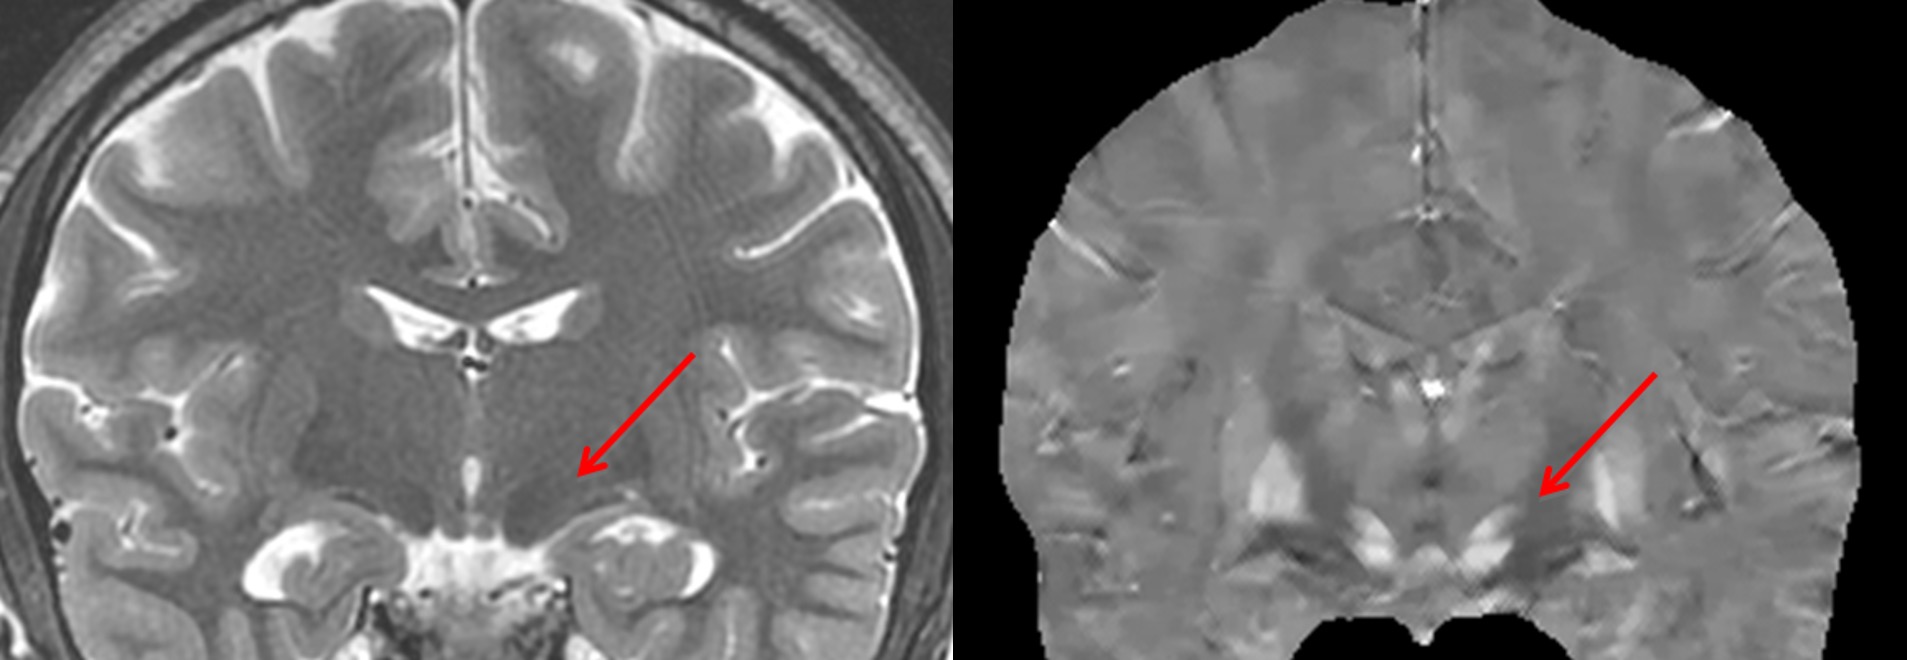

QSM can map iron involved in neuron function, including neurotransmitter generation. Deep gray nuclei are highly active in neurotransmitter generation with iron as a cofactor. Traditional T2 weighted imaging (left) depicts iron-rich deep gray nuclei such as subthalamic nucleus (arrow) with blurred hypointensity. QSM (right) depicts subthalamic nucleus with sharp positive contrast. QSM is the method of choice for mapping DBS targets.